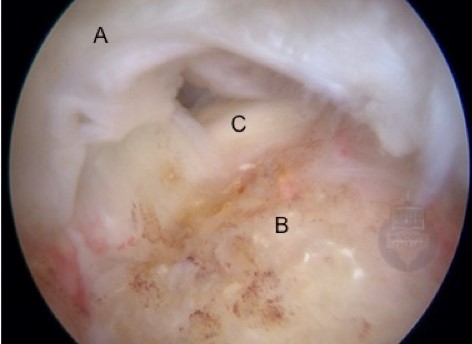

The rotator cuff tendons tear at their insertion into the humerus.  If a tear in the tendon goes through the full depth of the tendon then it is called a ‘full-thickness tear’.  If the damage involves only some of the thickness, it is termed a ‘partial-thickness tear’. Both can be painful and, because of this pain, impair function.  Full thickness tears tend to cause more significant weakness, as the connection between the muscle’s force and the bone is interrupted. The first image below shows a normal supraspinatus tendon (A) as it inserts onto the humeral head (B). The next two views show a medium-sized rotator cuff tear.  note how the tendon has peeled off from its insertion on the humerus, leaving exposed bone

Arthroscopic view of the same rotator cuff tear from the subacromial space. (A=rotator cuff tendon.

B = exposed bone on humerus where tendon should be inserting. C= visible cartilage on humeral head seen through tear)